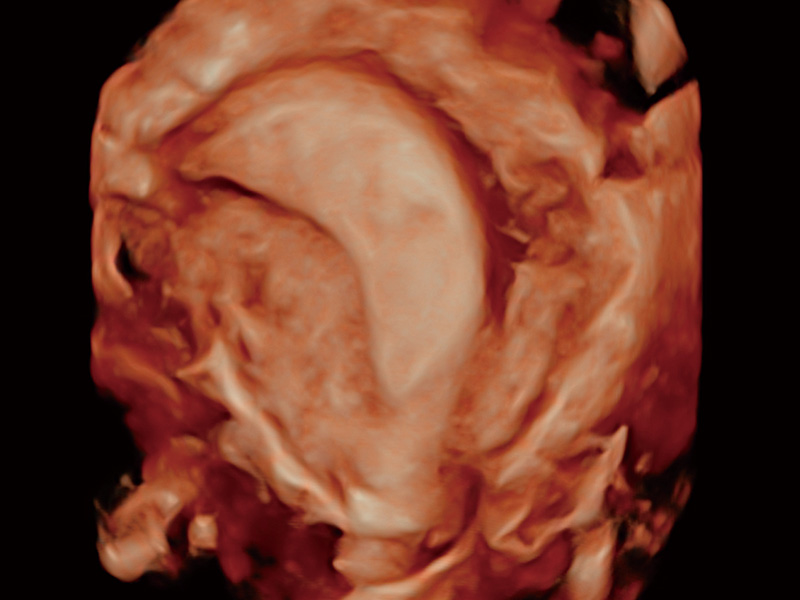

腔内容积探头

腔内三维成像技术获得显著提升,超大扇角在满足日常基础扫查的同时,支持卵泡自动测量及多种三维渲染模式,为您提供更多的诊断信息,尤其是在子宫畸形的诊断,内膜及肿瘤占位观测中起到了重要的作用。

临床图

子宫内膜息肉

输卵管间质部妊娠